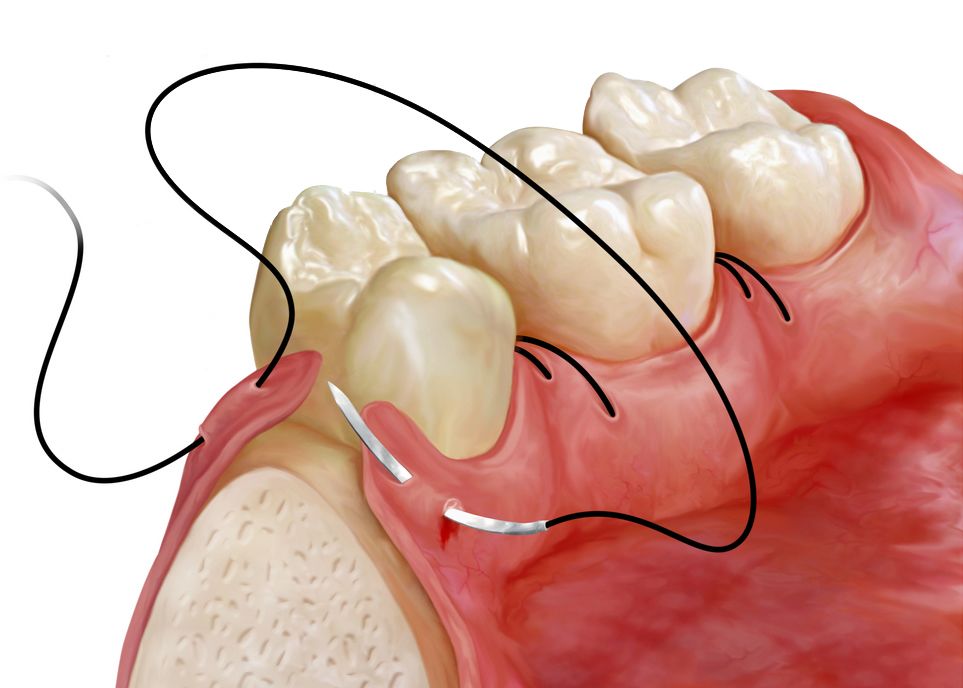

Flap Surgery

Patients with advanced gum disease may require flap surgery if more conservative periodontal treatments such as scaling and root planing are not sufficient. This procedure provides access to the roots and underlying structures that support the teeth to remove plaque and tartar and smooth bone.